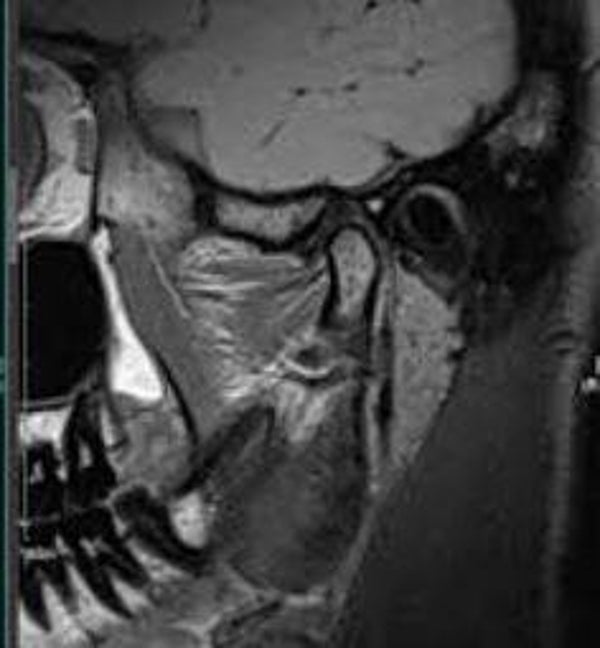

TMJ MRI

CA$50.00